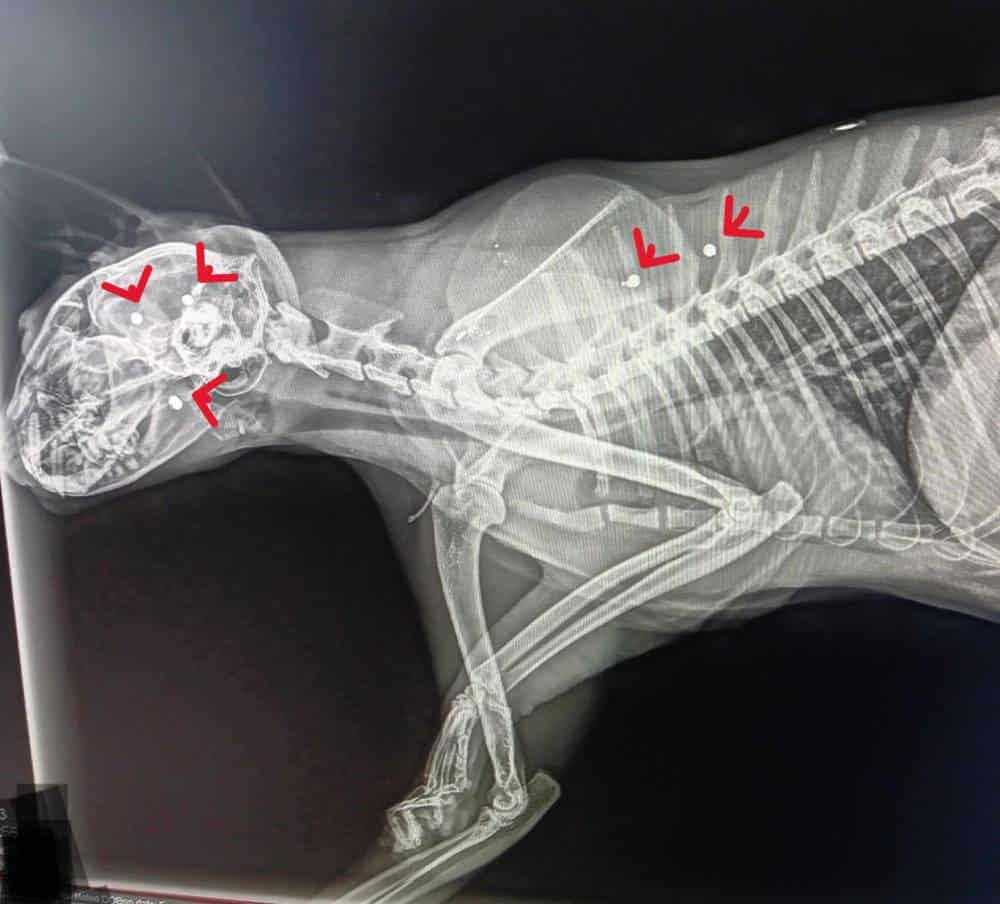

So at her next visit, the vet decided to take an x-ray.

They wanted to see if the pellet was still in her skull.

Because there were no obvious exit wounds.

They expected to find one piece of metal.

Just one.

But when the x-ray came back, the room changed.

Everyone stared at the image like their minds could not understand it.

The pellet was there.

And it was not alone.

There were many pellets lodged in her skull.

More in her jaw.

More scattered through her body.

That meant something no one wanted to say out loud.

Helen had not been shot once.

She had been shot multiple times.

Or shot with buckshot, sprayed like she was nothing.